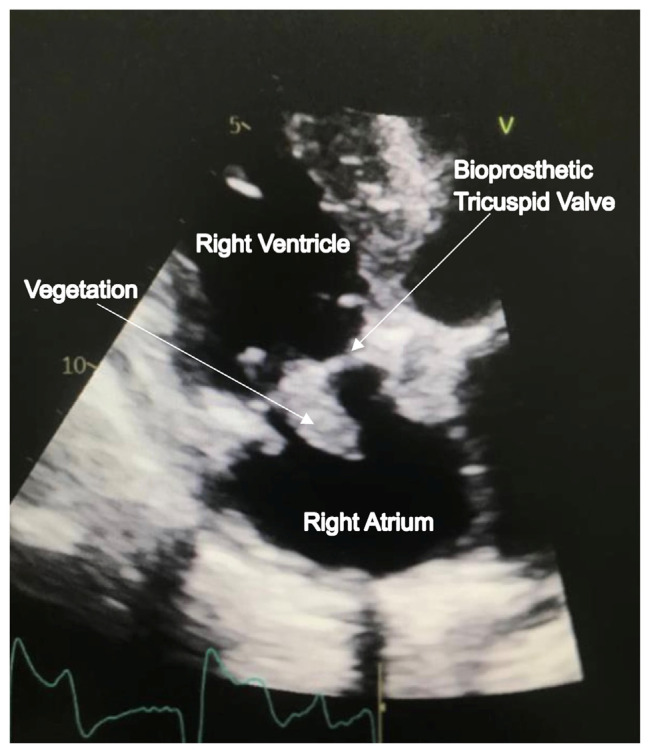

Fungal endocarditis (FE) is a rare yet life-threatening condition, especially in hemodialysis (HD) patients with indwelling long-term catheters. Symptoms often overlap with non-fungal infective endocarditis, making diagnosis difficult. As FE incidence increases, healthcare providers face challenges in diagnosing and managing this severe condition. Early suspicion of FE is crucial for patients with long-term catheters. We reported a 23-year-old male with end-stage renal disease (ESRD) on HD that developed FE affecting the tricuspid valve, requiring valve replacement and anti-fungal medication. Despite these interventions, he had recurrent Candida prosthetic endocarditis (CPE). Currently, he is receiving anti-fungal medication, with plans for a third surgery.